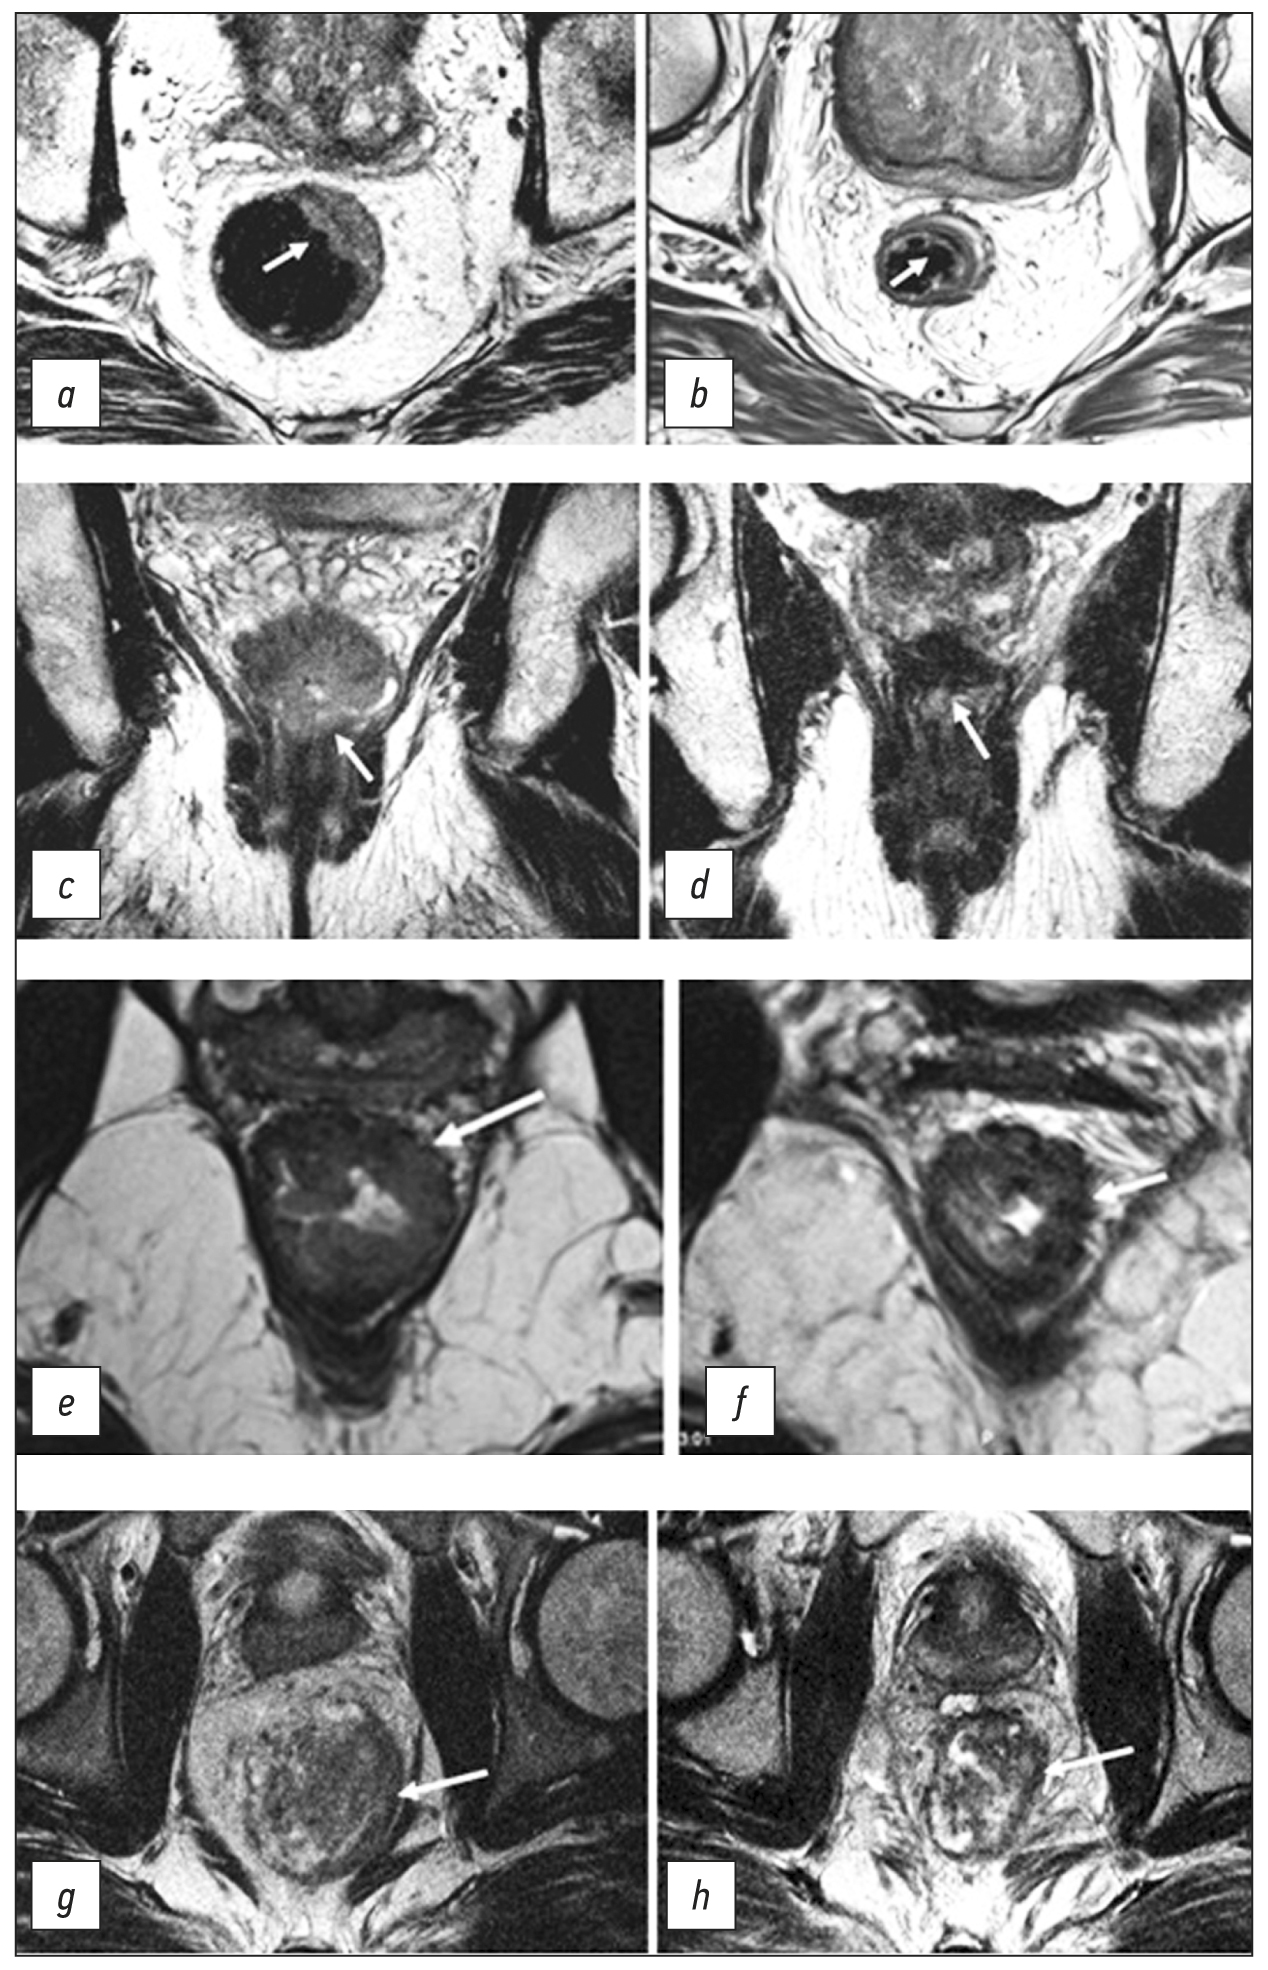

Mucinous cancer is a prognostically unfavorable histological variant of rectal cancer with tumor content of extracellular mucin >50% of the tumor volume. On MRI, mucin accumulations have a hyperintense signal on T2-WI (Fig. 3).

Fig. 3. Variants of tumor image on T2-WI. (a) Polypoid/exophytic tumor (arrow). (b) Semicircular tumor (T), extramural vascular invasion (arrows). (c) Mucinous tumor (arrows).

The tumor lesion is usually represented by ulceration/erosion in the center of the tumor, where the maximum depth of tumor invasion is determined.

Polypoid tumor is a tumor with an exophytic type of growth (Fig. 3). It may have a pedicle with clearly visible feeding vessels. The location of such a tumor can be indicated using a conventional dial (12 o’clock for the center of the anterior wall, 6 o’clock for the center of the posterior wall, 3 o’clock for the center of the left wall, and 9 o’clock for the center of the right wall).

A semicircular tumor occupies only part of the circumference of the rectum.

Circular/subcircular tumor spreads over the entire or almost entire circumference of the rectal lumen (Fig. 3).